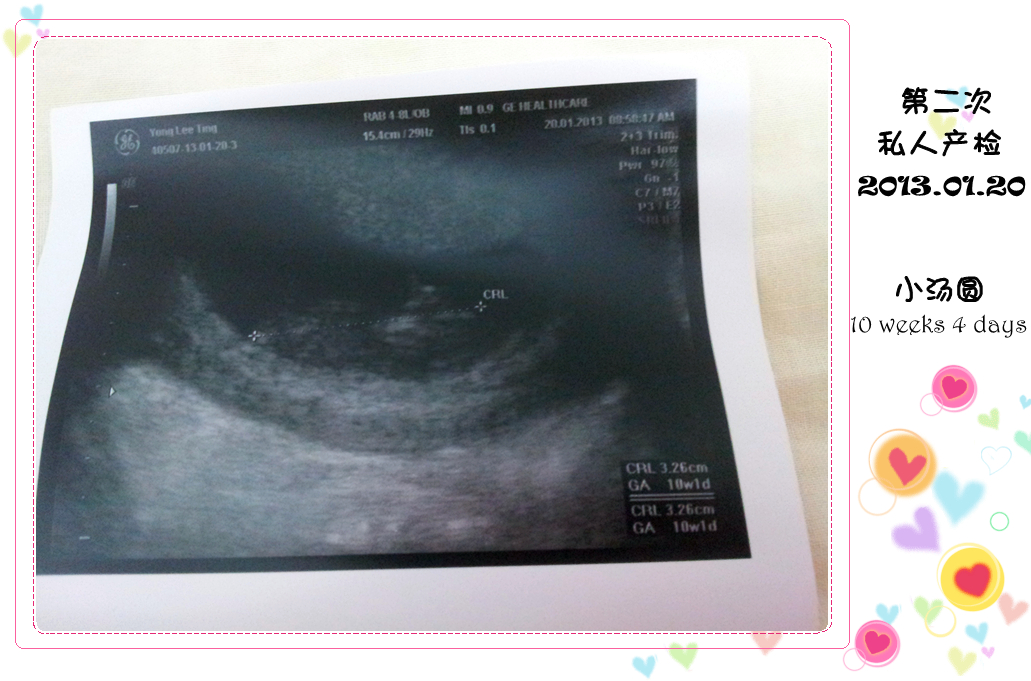

(๑•ᴗ•๑ )♡ 第二次私人产检 ♡(๑•ᴗ•&#3665

2013年01月20日,星期日

小汤圆:10 weeks 4 days (3.26 cm)

妈咪体重:55.2 kg

话不多说,赶快扫描看看小汤圆

医生一开始扫描的时候,我只看到一个宝宝的形

其他的什么也看不出

直到医生 zoom in 过后,才看到小汤圆的手和脚

而这小家伙,不知道是不是知道爹地妈咪在看他

他不停的摆动着小手和小脚,像是在和我们打招呼呢

看得我和老公兴奋不已,感动不已呢